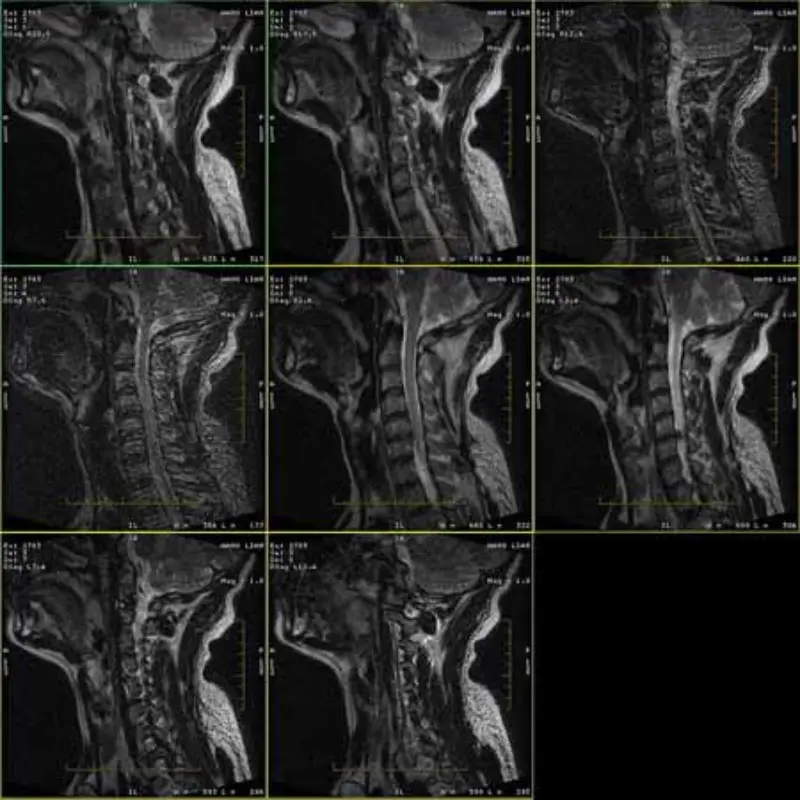

FRFSE eta GRE protokoloen irudiek mamuak dituzte eta batzuetan SNR baxuko irudiak serie batean agertzen dira. Baina SE protokoloaren irudiak normalak dira.

Mesedez, begiratu irudiak erantsi.